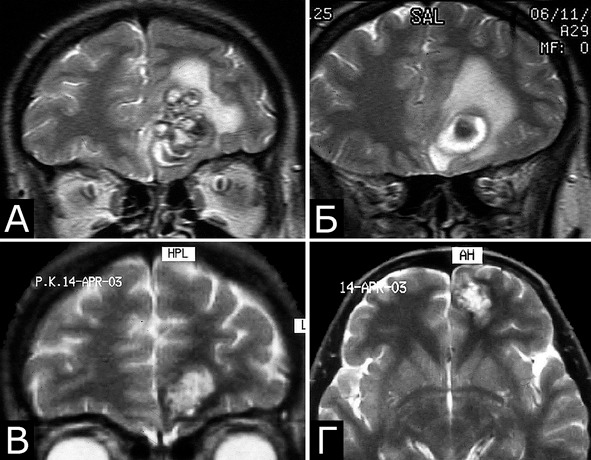

Рис. 29.II. Изменение размеров кавернозных мальформаций. КМ полюса левой лобной доли. А, Б – МРТ через 2 месяца после первого эпилептического припадка (режим Т1, фронтальная проекция). В, Г – МРТ через 7 месяцев после первого проявления заболевания. Объем КМ уменьшился, перифокальный отек регрессировал (режим Т2, фронтальная и аксиальная проекции)